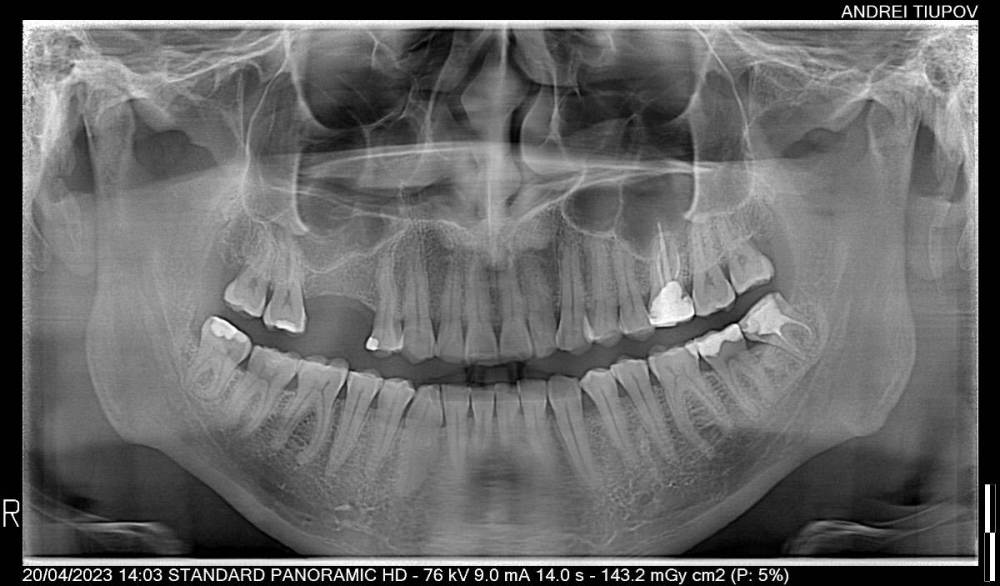

randomsctions Опубликовано 21 апреля, 2023 Поделиться Опубликовано 21 апреля, 2023 (изменено) Здравствуйте! Около 10 дней назад появилась стреляющая боль в верхней части челюсти слева. Сходил ко врачу (терапевту), результат: боли неясного характера. выписали дексаметазон и сказали наблюдать. На время стало меньше болеть. два дня назад сильно заболело в области, обведенной красным на снимке. Сначала казалось, что это зуб с большой пломбой, теперь, спустя два дня непрерывной интенсивной боли уже тяжело сказать, откуда именно исходит боль. Болит очень сильно, на 9 точно, почти невозможно терпеть. Не спал двое суток, и непонятно, когда удастся. Принимал по несколько таблеток кетарола, кетанова и ибупрофена, почти никакого эффекта, уснуть невозможно. вчера посетил утром другого врача (т.к. у первого не было номерков) - сделали снимок, сказали, точно не могут определить, с каким зубом проблема, и не хотят просто так пломбировать каналы здоровых зубов. Сказали, что боль может иррадиироваться от восьмёрок, и их можно попробовать удалить, но тоже не факт, что поможет. Выписали непраксен и антибиотики на 5 дней, записали на следующую неделю. Боль нестерпимая, поэтому в этот же день пошел в третью клинику. Надеялся, что удалят две восьмерки слева, и если боль не пройдёт, то уже смотреть дальше. Но врач отказалась удалять что-либо, а сказала, что 99%, что из-за стирания эмали и оголения дентина у зубов повысилась чувствительность, и отсюда боль (бруксизм у меня действительно есть, и зубы сильно стёрты, и часто реагируют на температуру или даже прикосновения). Покрыли сразу много зубов раствором для пломб, и отправили домой. В течение 2-3 часов я не чувствовал боль из-за анестезии (это были лучшие два часа за всё это время). Но сразу после этого разболелось ещё сильнее. Я уже не знаю, как мне это пережить, т.к. боль такая, что абсолютно невозможно уснуть. Уже готов удалить любое количество зубов, лишь бы избавиться от боли. Но если считать 4 обведенных красным зуба плюс пятый — 8ка снизу, то, как я понимаю, сразу 5 зубов удалять никто не станет. очень прошу подсказать, что тут можно сделать. Если это не решится за максимум ещё два дня, я не знаю, как я буду дальше. Не спать пятые сутки уже будет невозможно. Я готов удалить зуб(ы), но какой? Изменено 21 апреля, 2023 пользователем randomsctions Дополнение про бруксизм Ссылка на комментарий

randomsctions Опубликовано 22 апреля, 2023 Автор Поделиться Опубликовано 22 апреля, 2023 Стучали все три врача, но разницы никакой я не заметил. вчера сделали тест: ввели небольшое количество анестетика под каждый зуб с перерывом в 10 мин, чтобы посмотреть, когда утихнет боль. идентифицировали вот этот зуб таким оьразом (оьвёл красным на картинке). Удалили нерв и запломбировали канал. Боль изменилась, но не прошла. Накатывает волнами теперь от почти 0 до 7 по 10-бальной шкале, с периодом около 30 мин +-. Но хотя бы могу спать теперь. Всё ещё буду рад советам, т.к. до сих пор непонятно, в чем проблема. Ссылка на комментарий

randomsctions Опубликовано 24 апреля, 2023 Автор Поделиться Опубликовано 24 апреля, 2023 Добрый день! Наконец-то уговорил врачей сделать КТ. При постукивании, если внимательно прислушиваться, выделяется нижний зуб (обвел красным), ну и верхний депульпированный. Дантист быстро показала КТ эндодонтисту, оба врача ничего страшного там не увидели. Боль продолжается, в состоянии покоя снижается до 1-2, после еды или воды возрастает до 7-8, потом плавно возвращается к 1-2. 741021604_AndreiTiupovCBTCscan.dcm Ссылка на комментарий

Carioznik Опубликовано 25 апреля, 2023 Поделиться Опубликовано 25 апреля, 2023 (изменено) 22.04.2023 в 18:08, randomsctions сказал: Удалили нерв и запломбировали канал сейчас там временная пломба? Судя по КТ - каналы не до конца сделаны. (от этого могут сохраняться боли) На зубе 26 (верхний с большой пломбой) - приличный очаг воспаления из-за пропущенного, когда-то при лечении зуба, канала. Каналы в нём перелечить можно , но есть вопрос с восстановлением и дальнейшим прогнозом (от зуба скорее всего ничего не останется и восстановить его уже не получится нормально , соответственно есть вероятность удаления зуба) 18 часов назад, randomsctions сказал: При постукивании, если внимательно прислушиваться, выделяется нижний зуб Возможно есть рецидив кариеса под пломбой , но это только предположение, нужен очный осмотр. (вряд-ли он причина ваших проблем, но я бы взял его на заметку) еще бы верхний предпоследний более детально посмотреть (очно и доп.прицельный снимок) пока вывод такой: долечить зуб , где удалили нерв. Далее переходить к верхнему зубу с большой пломбой. PS сделайте хоть фотографию во рту, если получится. может что-то еще прояснится Изменено 25 апреля, 2023 пользователем Carioznik 1 Ссылка на комментарий